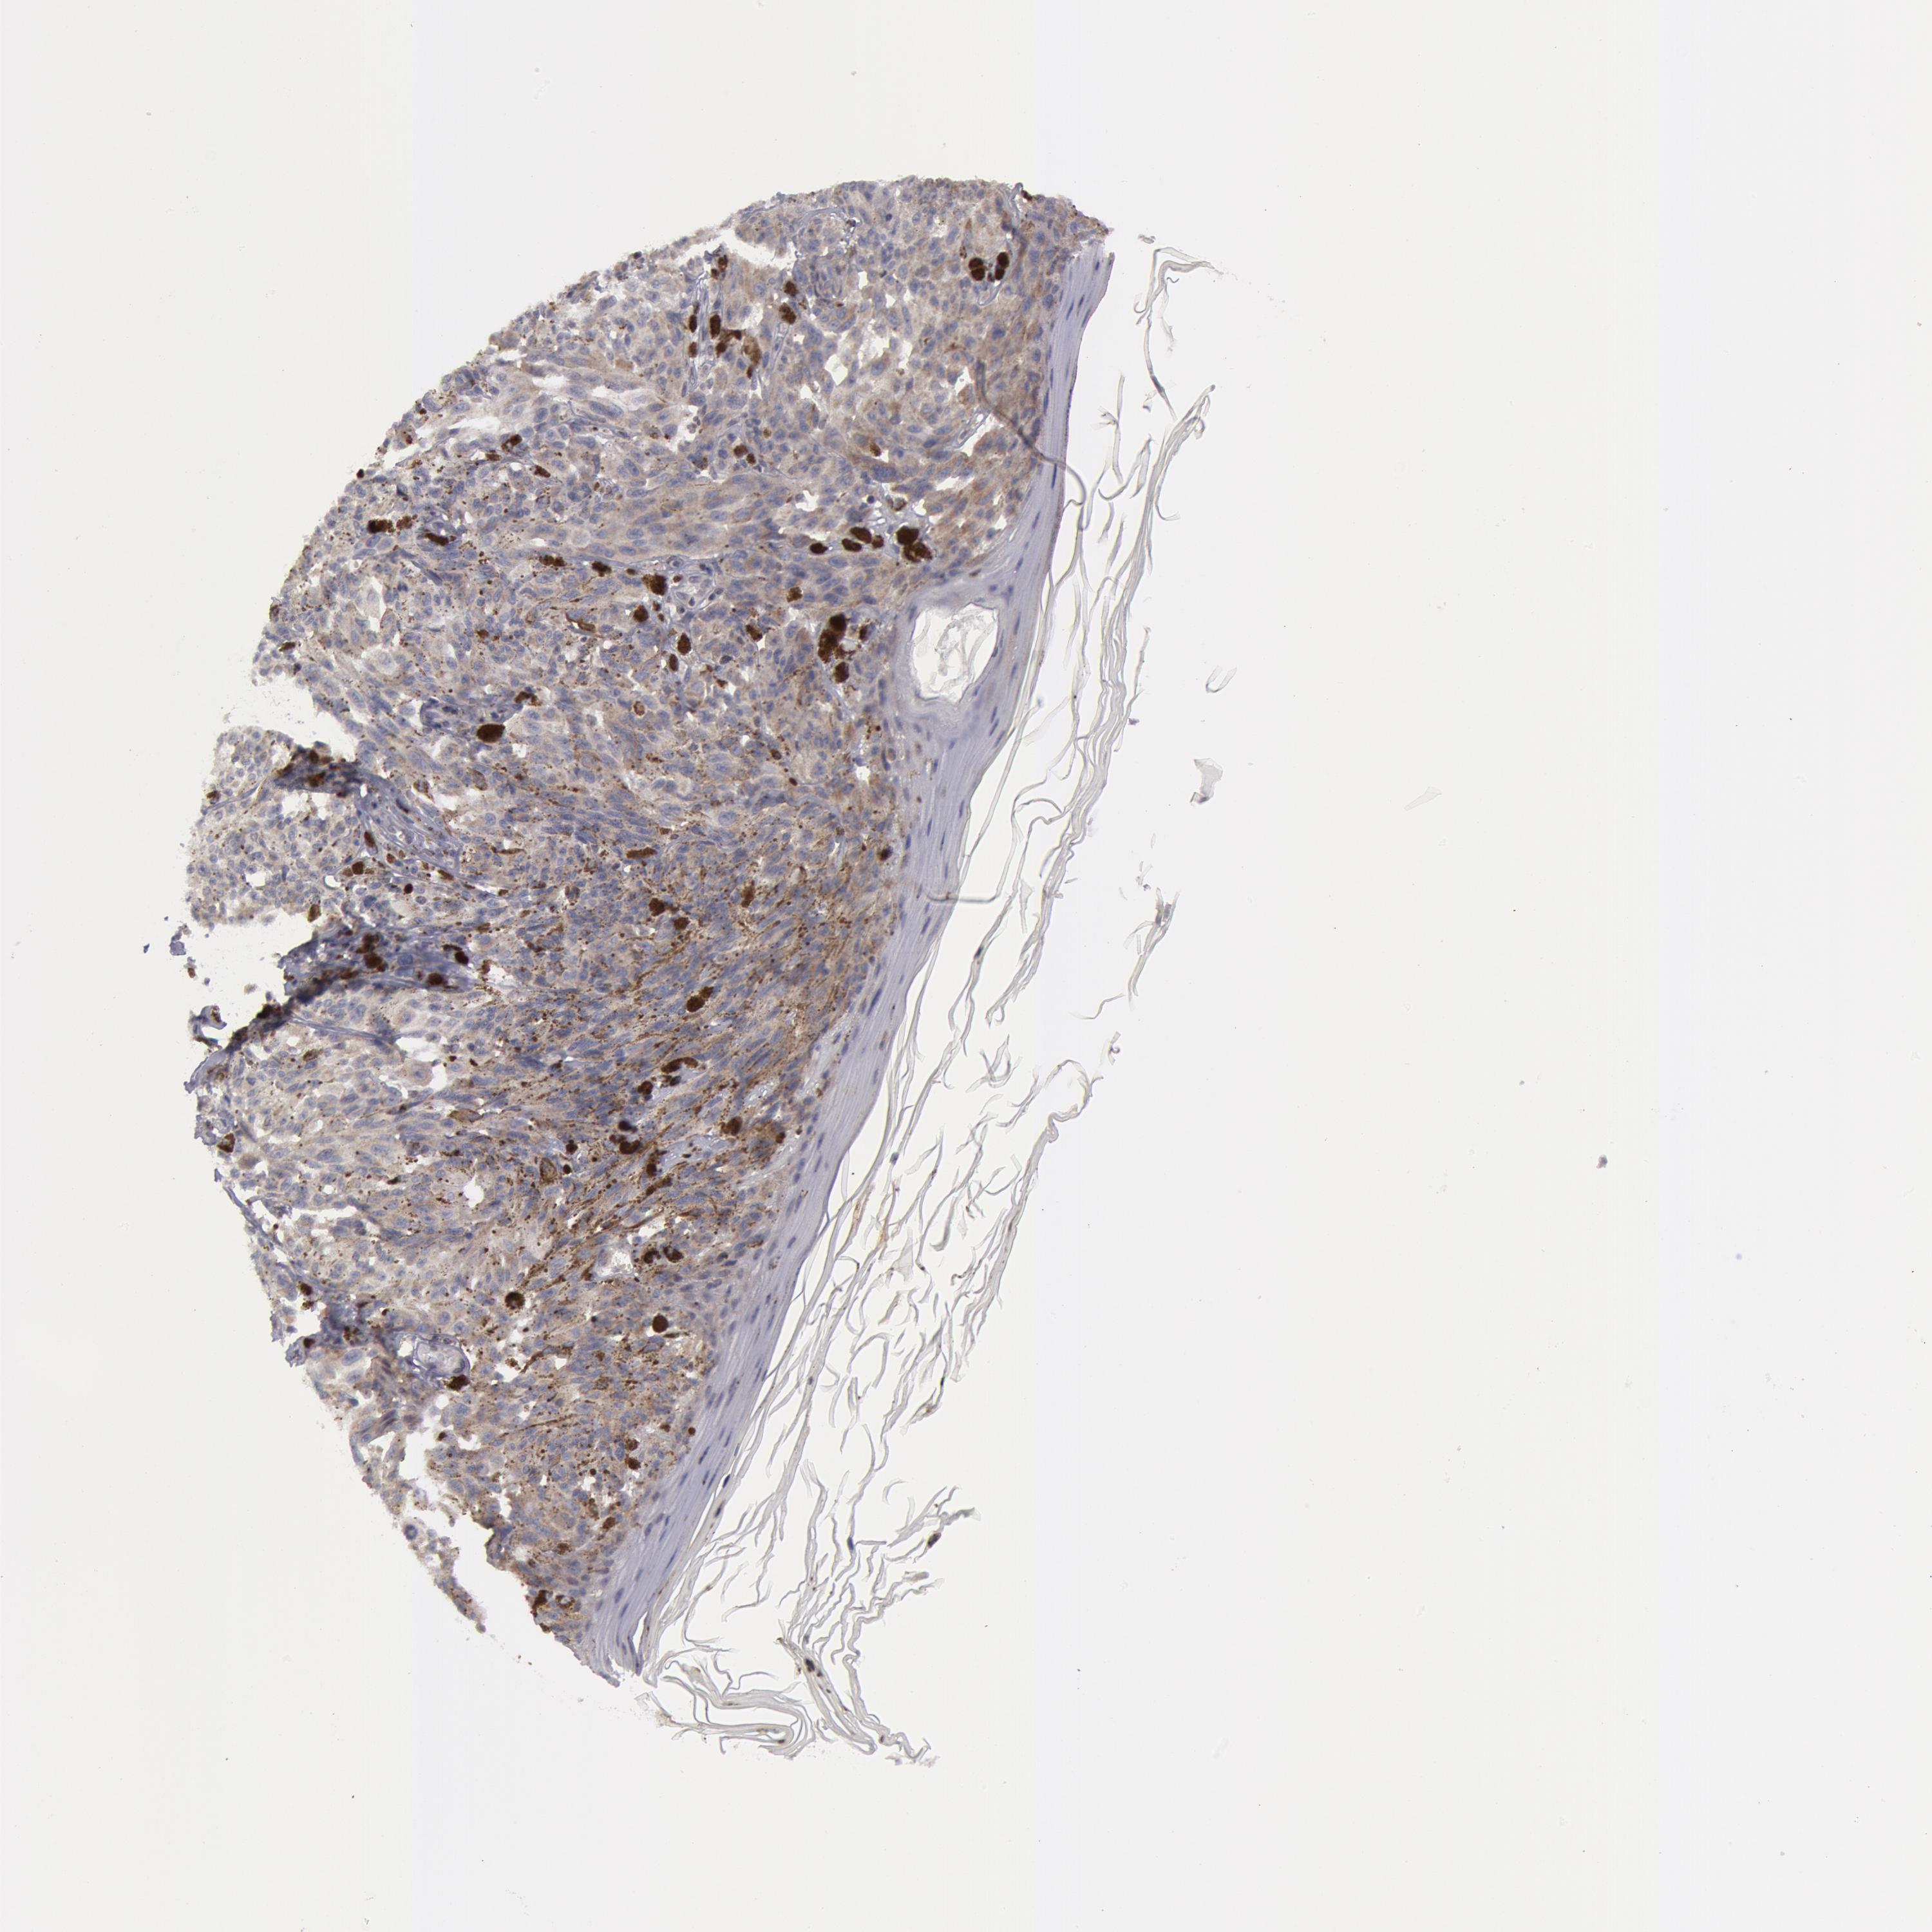

MELANOMA - Protein expressioni

A mouse-over function shows sample information and annotation data. Click on an image to view it in a full screen mode. Samples can be filtered based on level of antibody staining by selecting one or several of the following categories: high, medium, low and not detected. The assay and annotation is described here.

Note that samples used for immunohistochemistry by the Human Protein Atlas do not correspond to samples in the TCGA dataset.

Antibody stainingi

Antibody staining in the annotated cell types in the current human tissue is reported as not detected, low, medium, or high, based on conventional immunohistochemistry profiling in selected tissues. This score is based on the combination of the staining intensity and fraction of stained cells.

Each image is clickable and will lead to virtual microscopy that enables deeper exploration of all samples and also displays staining intensity scores, fraction scores and subcellular localization as well as patient and tissue information for each sample.

Malignant melanoma, NOS

Malignant melanoma, Metastatic site